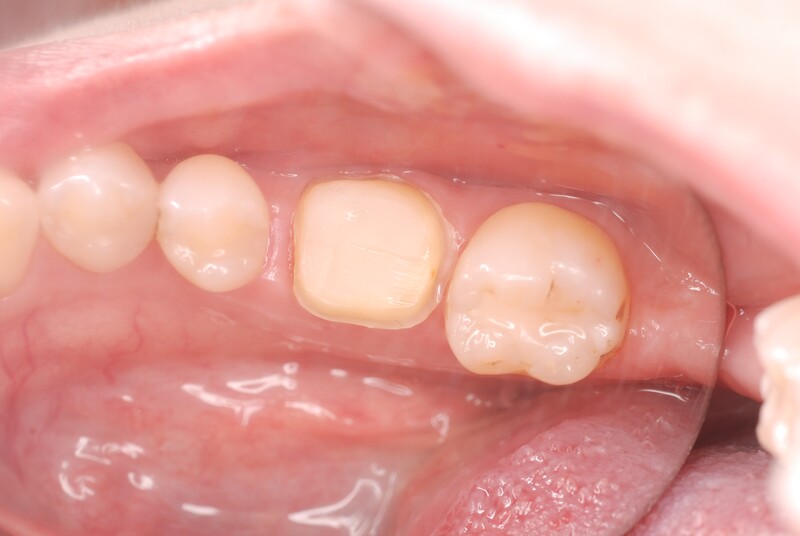

初診時の状態です。歯肉に腫脹が認められます。

被せ物を外すと歯の神経である歯髄は死んでしまっており、歯に亀裂も認められます。

亀裂を樹脂で補強し、ラバーダム防湿下で根管治療を開始しました。

状態が改善したことを確認し、最終的な被せ物を装着しました。